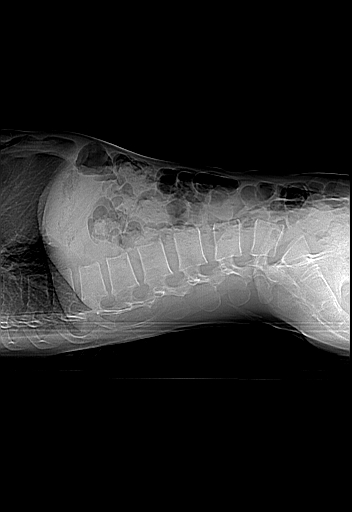

男,31岁,从6米高处坠落伤两天,腰背部疼痛,临床要求ct扫描胸10-腰1。请大家帮忙看看骨质有问题吗?

t12、l1锥体前缘轻度楔形变,平扫示椎体前缘骨小梁欠规整,第9幅图示椎体前缘骨质不连续,结合外伤史考虑椎体轻度压缩骨折。

楼主扫描层厚可能较大,每个椎体只有三个层面.

从所示层面分析,无明确骨折征象,象类似病人我个人会建议mri除外骨挫伤.